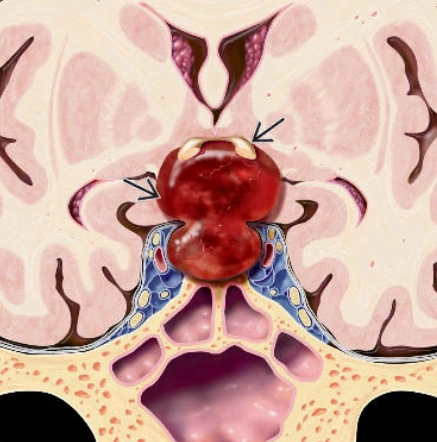

• Đột quỵ tuyến yên (Pituitary apoplexy)